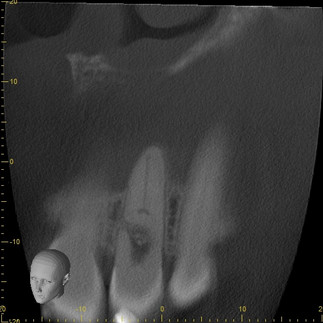

At first glance, the PA appears to show internal resorption on 10. The CBCT that was acquired on this patient (using the J. Morita X800 F40) shows a different situation:

The CBCT scan made clear that this was actually a more rare case of internal resorption that had progressed into replacement resorption. Progressing through the scan, you can actually see that the bone has regrown in such a way that it has completely separated the crown from the apex of the tooth, fundamentally changing the treatment plan for this patient.